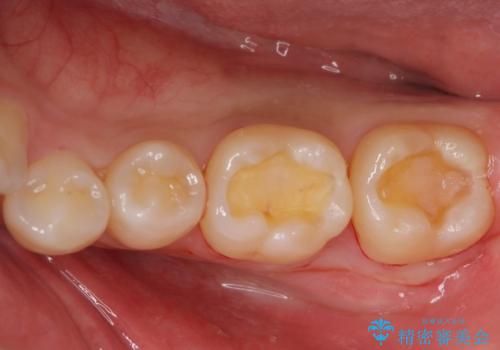

- 歯に穴が空いているとの事で来院。

セラミック、ゴールドの詰め物のご案内をしたところゴールドを希望されたのでゴールドインレーで治療を行いました。